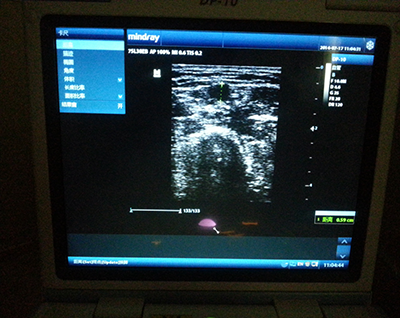

护士长通知B超室工作人员在B超室等候患者,随后为患者测量肘横纹以上10cm的上臂围,记录测量数值并开始置管。置管完毕后,为确保管路置入位置的准确性,经彩超显示、冲管、回抽静脉血、胸部拍片,反复确认置管成功。经过大家的全力配合,PICC置管顺利,术中患者无不适,术后患者安返病房。